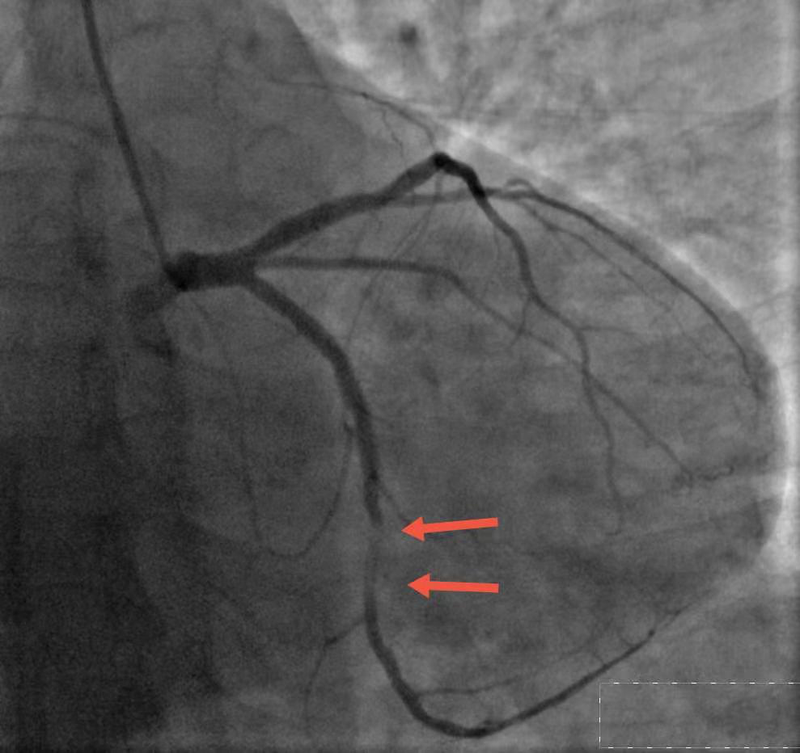

患者为51岁男性,主因“发作性胸憋半月”入院,术前诊断为:冠心病,急性非ST段抬高型心肌梗死。冠状动脉造影显示:左冠回旋支中段“模糊病变”,狭窄程度大于80%-90%,病变性质不清楚,符合OCT进一步评价的指征。